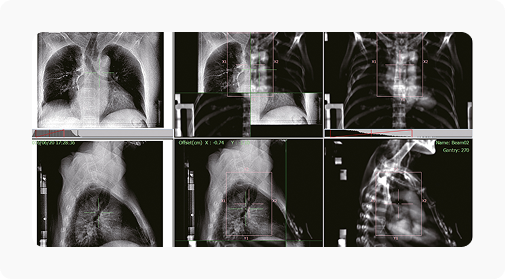

Технологии визуализации и контроля: kV CBCT, MV EPID и BPS (авторская SGRT-система LinaTech).

ИИ совмещает kV CBCT, MV EPID и BPS изображения, чтобы повысить точность облучения.

| Система визуализации | kV-CBCT , MV-EPID |

| Максимальное поле обзора CBCT [см] | 35 |

| Разрешающая способность CBCT [пара линий/см] | ≥12 |

| Разрешение матрицы детектора | 2816х2816 |